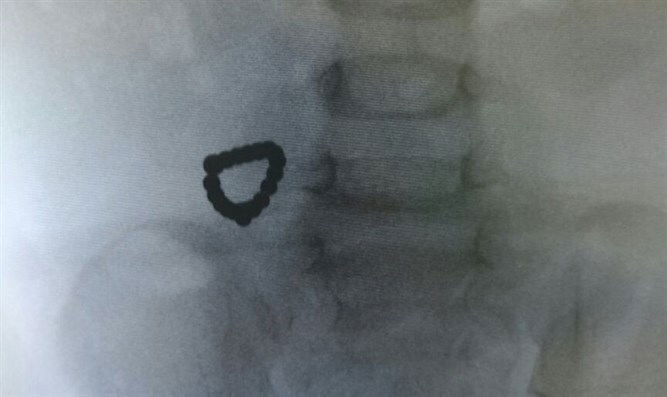

יצויין, כי תחילה חשד הצוות הרפואי בבית החולים כי הסיבה למצבו של הפעוט היא בכלל חסימת מעיים. ד"ר אדריאנה ניקה, כירורגית ילדים בכירה בשניידר, מסבירה: "קראו לי ישר למחלקה, אחרי שהצילום העלה ממצאים שישנה שרשרת עם כ-40 מגנטים בגוף של הילד. בגלל שהאימא אמרה שאין שום סיכוי שיש בבית מגנטים אז חשבנו בהתחלה שהוא בלע שרשרת קטנה רגילה, אבל במשך 24 שעות הוא עבר מספר צילומים בבטן וראינו שאין תזוזה, השרשרת לא זזה וזה כבר לא סביר לשרשרת רגילה".

בבטנו של פעוט בן שנתיים, שהובהל לאחרונה לבית החולים שניידר בפתח תקווה לאחר שהקיא וחש ברע, נמצאה שרשרת ובה 40 מגנטים.